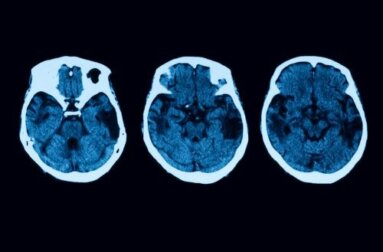

Diese Tests zur Erstellung einer ordnungsgemäßen Diagnose reichen noch lange nicht aus. Um jeden Zweifel auszuräumen, führen die Spezialisten neurologische Tests, einschließlich einer Magnetresonanztomographie (MRT) und einer Computertomographie (CT), durch. Erst wenn alles darauf hindeutet, dass wir einen Fall von posteriorer kortikaler Atrophie vor uns haben, beginnt die entsprechende Behandlung.